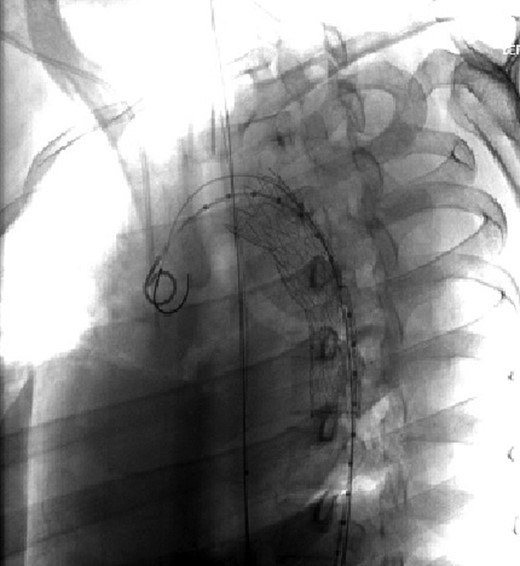

The patient was taken emergently to the vascular hybrid room where the left common femoral was accessed percutaneously. A 26–21 mm diameter tapered Gore Tag® endograft was positioned at the left subclavian artery and deployed. The pseudoaneurysm was sealed and the transection resolved (Figs 2 and 3).

Visualization of the aortic arch and thoracic aorta after stent placement.